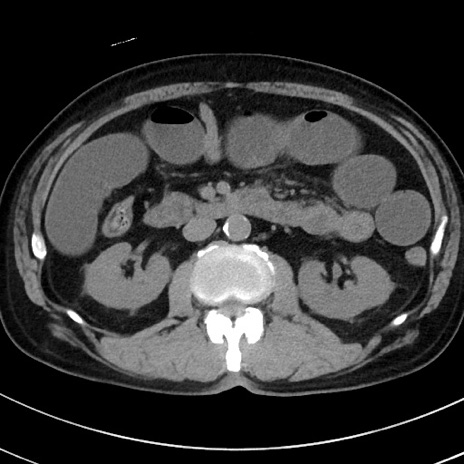

症例38(横断像)

【症例】70歳代 男性

【主訴】腹痛・嘔吐

【現病歴】昨晩より、嘔吐・腹痛あり。今朝になっても嘔吐あり。来院。

【既往歴】心臓バイパス手術、開腹胆摘、腸閉塞

【身体所見】BP 107/71mmHg、HR 116/min、腹部:平坦、軟、下腹部に軽度圧痛あり。反跳痛なし。

【データ】WBC 15100、CRP 0.32